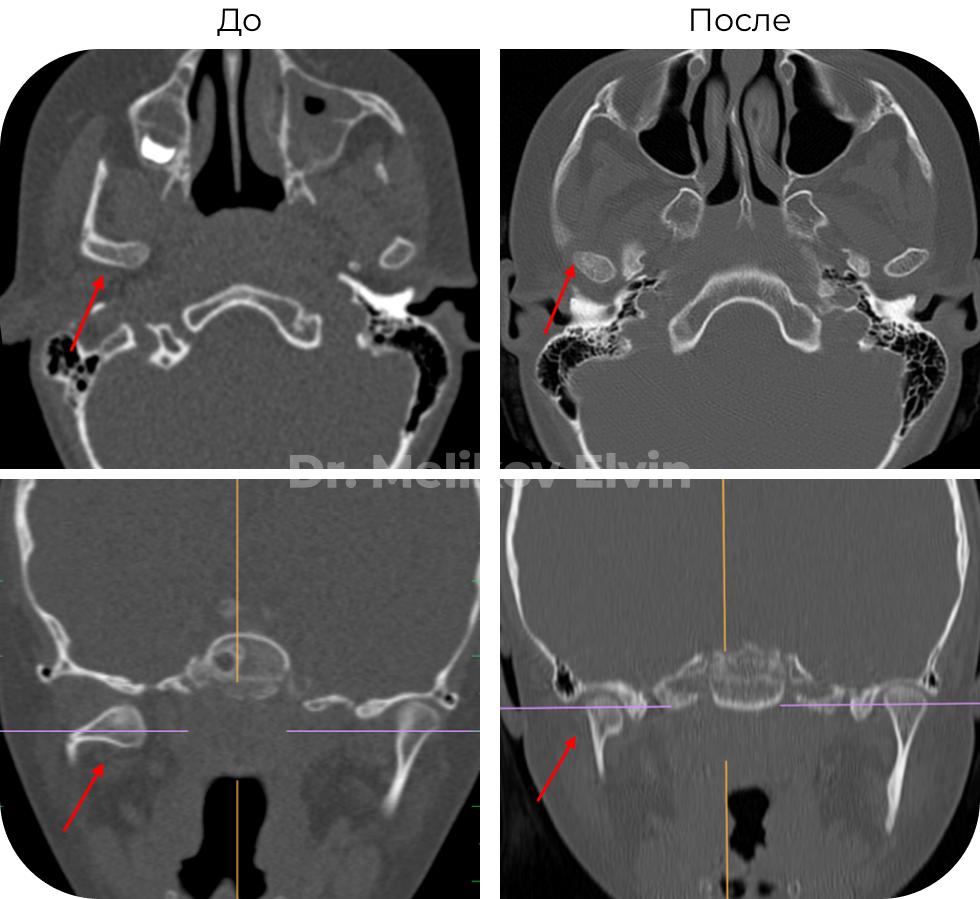

Безоперационное лечение перелома правого мыщелкового отростка нижней челюсти у ребенка 7 лет

🔹Диагноз: Перелом правого мыщелкового отростка нижней челюсти.

🔹Что получили: При дистракции правого внчс, под действием мышц, отросток репонировался и произошла полная консолидация.

До и после лечения